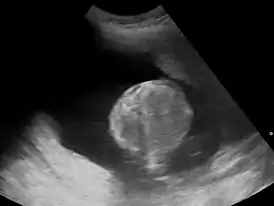

Многоводие (синоним греч. полигидрамнион) — патологическое состояние, при котором наблюдается избыток околоплодных вод в амниотической полости. По статистике, наблюдается у 1% беременных женщин.[3][4][5] Существует два типа многоводия: